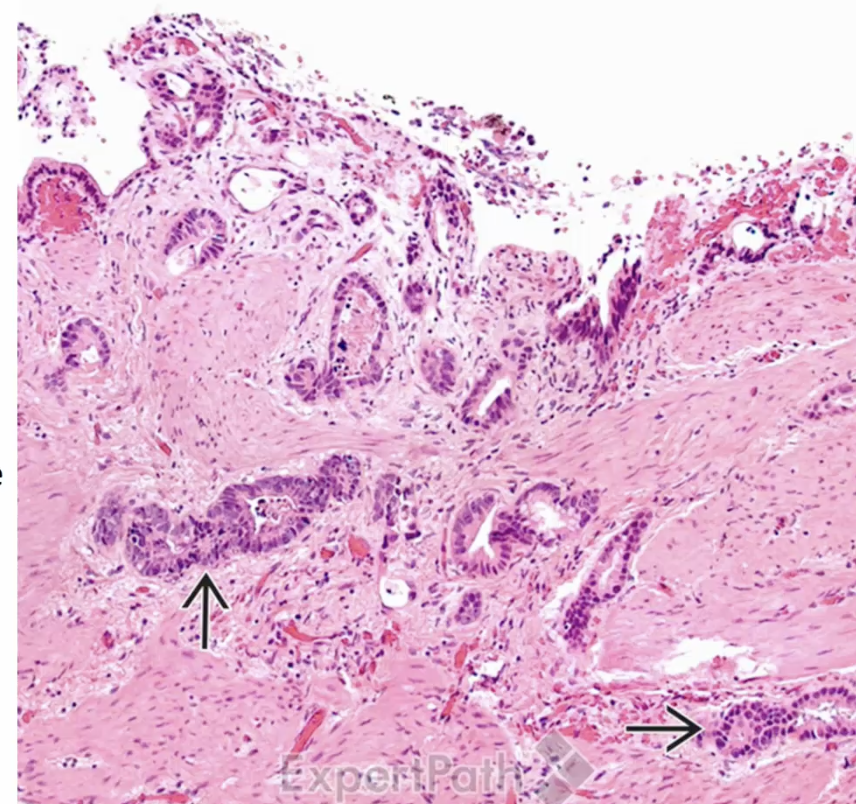

Rokitansky-Aschoff Sinuses

small pouches that form in the gallbladder wall, often associated with chronic cholecystitis. They can contribute to inflammation and dysmotility of the gallbladder.

Chronic cholecystitis

Adenocarcinoma of the Gallbladder

Extrahepatic Cholangiocarcinoma